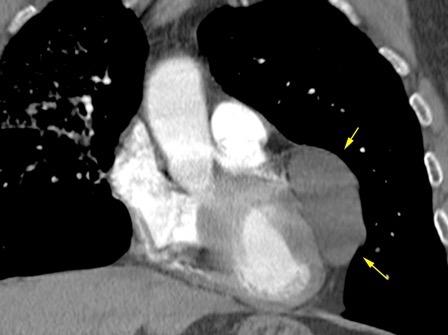

102. HEMATOMA MEDIASTÍNICO.

Rotura traumática aórtica.Hematoma toracoabdominal